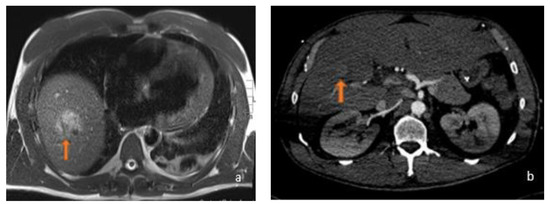

5. Malignant MRI Features

5.1. FLL Feature Characteristic

5.2. LFF MRI Radiomic Features OS and Response to Therapy

6. Benign MRI Features